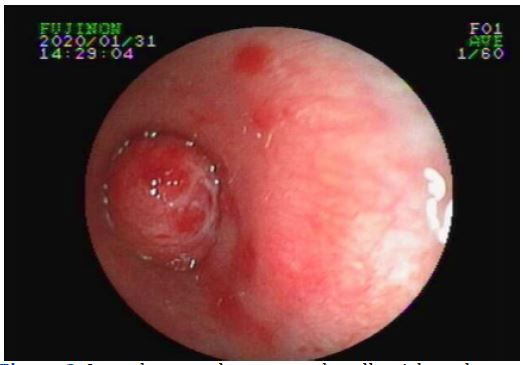

In order to determine the nature of the left main bronchus nodule, bronchoscope was carried out on February 4, 2020. Under the microscope, it can be seen that a smooth, yellowish, pedunculated new biological occluded the bronchi (Figure 2).

Figure 2: It can be seen that a smooth, yellowish, pedunculated new biological occluded the bronchi in bronchoscope.